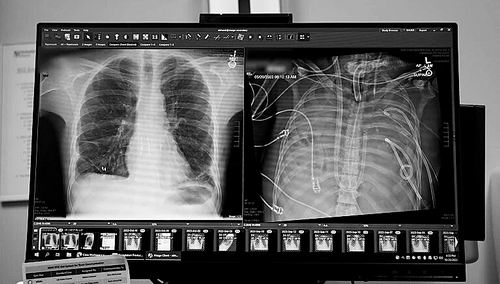

X光片显示的一名33岁患者的新肺(左)和旧肺。

令人惊讶的是,这名男子的病情很快有了好转。“在48小时内,他停止了所有维持血压的药物治疗,肾功能完全恢复,心脏也开始正常工作。”Bharat说。随后,该男子接受了双肺移植手术,也没有出现器官排斥或肺功能受损的迹象。“从我们进行这项手术到现在已接近3年,患者状况非常好。”